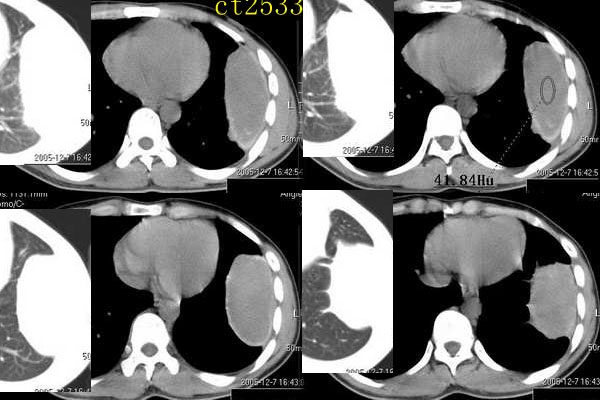

ct2533:张巍 提供 患男,24岁,胸痛数月.

穿刺活检为干酪坏死物.胸壁结核瘤!